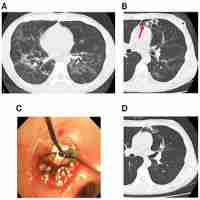

| Abstract | Background Massive hemoptysis is a common encounter in respiratory medicine. Bronchoscopy plays an important role in localizing the origin of bleeding, as well as endoscopic treatment of centrally located lesions. Endobronchial embolization is a novel technique enabling the management of hemoptysis arising even from peripheral lesions, via occlusion of the culprit bronchus, thereby securing the airway. Endobronchial Watanabe Spigot had been advocate in the treatment of bronchopleural fistula and the use of this novel technique had since then been expanded into the management of massive hemoptysis. To the best of our knowledge, this is the first reported case in Malaysia. Case presentation 78-year-old lady who presented with life-threatening hemoptysis leading rapidly to cardiac arrest upon arrival. Spontaneous circulation was restored after resuscitation with an urgent thoracic computed tomography angiogram revealed bleeding likely from the posterior basal segment of left lower lobe, with bronchiectatic changes. Urgent flexible bronchoscopy revealed airway flooding, with bleeding originating from the lingular and posterior-basal segment of the left lower lobe. Airway toileting was performed and two 7 mm Endobronchial Watanabe Spigots were plugged into the culprit bronchi. Urgent bronchial artery embolization was then attempted, but was unsuccessful. She was managed conservatively, as surgical resection was deemed high risk. The spigots were removed 4 days later uneventfully. There was no recurrence of hemoptysis, and patient remained well during 1-month follow up. Conclusions The utmost priority in managing life-threatening hemoptysis is to prevent airway flooding. Endobronchial embolization with Endobronchial Watanabe Spigot is useful as a temporary measure before definitive therapy, or can itself be the main therapeutic player in the hemoptysis armament for high-risk patients. |